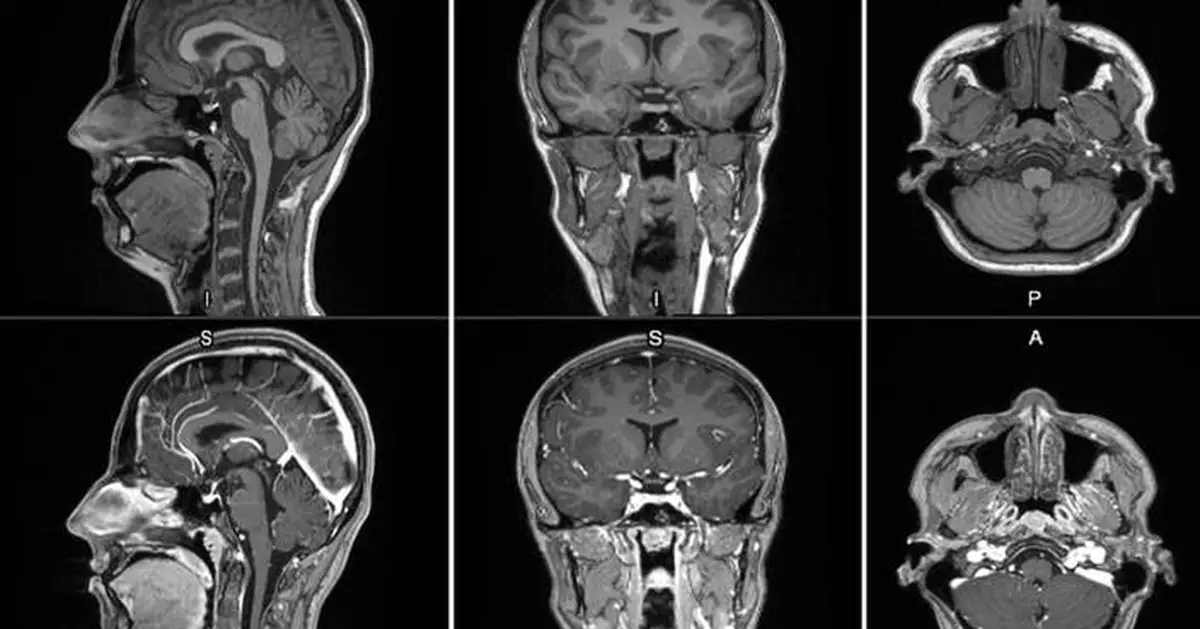

First-in-human contrast enhanced MRI images with GE HealthCare's mangaciclanol

GE HealthCare (Nasdaq: GEHC) today announced the first patient has been dosed in the international, multi-center Phase 2/3 LUMINA clinical trial of its manganese-based magnetic resonance imaging (MRI) contrast agent, mangaciclanol, at Mayo Clinic in Rochester, Minnesota. Mangaciclanol, if approved, could offer an alternative to – or even replace – gadolinium-based MRI contrast agents, the current standard of care. The investigational agent has been granted Fast Track designation by the U.S. Food and Drug Administration (FDA) for use in adults and pediatric patients aged 2 years and older with MRI to detect and visualize lesions with abnormal vascularity in the central nervous system and the body. FDA Fast Track designation expedites the review of new therapeutics and medical imaging agents that have the potential to address significant unmet patient needs.

MRI contrast agents enhance the visualization of abnormal structures or lesions during imaging procedures and help clinicians better distinguish between healthy and diseased tissue. Mangaciclanol is intended for general-purpose MR imaging and demonstrates comparable relaxivity (the ability to enhance signal intensity) to market-leading gadolinium-based agent, gadobutrol, with early clinical images suggesting similar diagnostic capability. Unlike gadolinium, which is a rare-earth metal, manganese is present in our food, and is an endogenous element, naturally occurring and autoregulated in the body. The macrocyclic ‘cage-like’ structure of mangaciclanol lessens the possibility of retention.